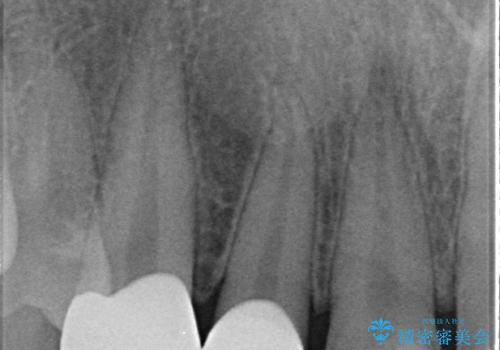

- 右上2、3番目の歯の色・形が気になるといらっしゃった方の症例です。

古い樹脂を除去後、オールセラミッククラウンによる補綴を行いました。